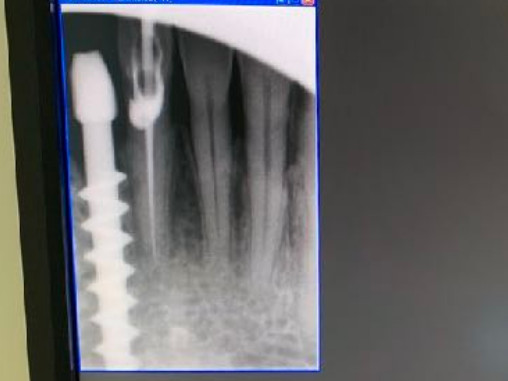

N.impianti esistenti

4

Tipo di impianto

Tramonte

N.impianti inseriti

1

41

App.Rx endorale

VixWin Guidizzolo

Tac

presente